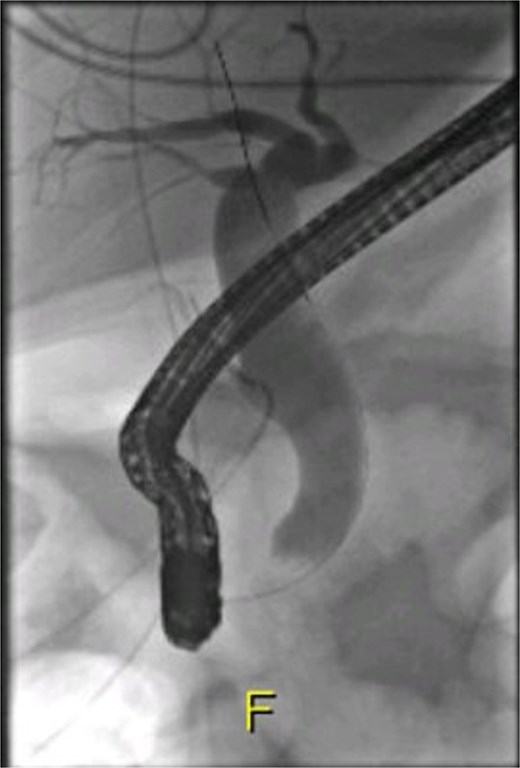

Following a brief clinical response to the initial conservative management for 24 hours, the patient started deteriorating and developed generalized peritonitis with worsening of inflammatory markers (C-reactive protein escalated to 438 mg/l). Consequently, she underwent an emergency diagnostic laparoscopy as the cause of peritonitis was not clear. Intraoperatively, it was observed that there was free bile in the peritoneal cavity, more so around the liver and the right paracolic gutter. There was also a bile collection behind the right colon and hepatic flexure of the colon, raising the possibility of a retroperitoneal source. The hepatic flexure of the colon was mobilized to assess the source of the leak. No obvious ongoing leak was noticed. As a precautionary measure, an Upper GI endoscopy was conducted intra-operatively to rule out any gastroduodenal perforation, as no obvious source of bile leak was seen from the biliary tree. This revealed the presence of bile in the stomach and confirmed normal anatomy up to the third part of the duodenum. The remaining intra-abdominal organs appeared unremarkable. Thorough peritoneal lavage was given, and 22 Fr abdominal drains were placed in the subhepatic, para-hepatic space, and pelvis, respectively, as the source of leak was not found. The following day, an endoscopic retrograde cholangiopancreatography (ERCP) was performed, which identified a small leak around the area of the cystic duct stump (Fig. 3). In response, a 5 cm-sized 7 Fr double pigtail stent was inserted into the CBD. A post-ERCP CT scan was performed to evaluate the contrast leak. The CT imaging revealed an extraluminal contrast leak originating from a defect in the posterior CBD (Fig. 4). Notably, the cystic duct stump remained intact and anterior, establishing the diagnosis of Spontaneous biliary leak from the CBD.

ERCP imaging reveals contrast leak in the cystic duct stump region.